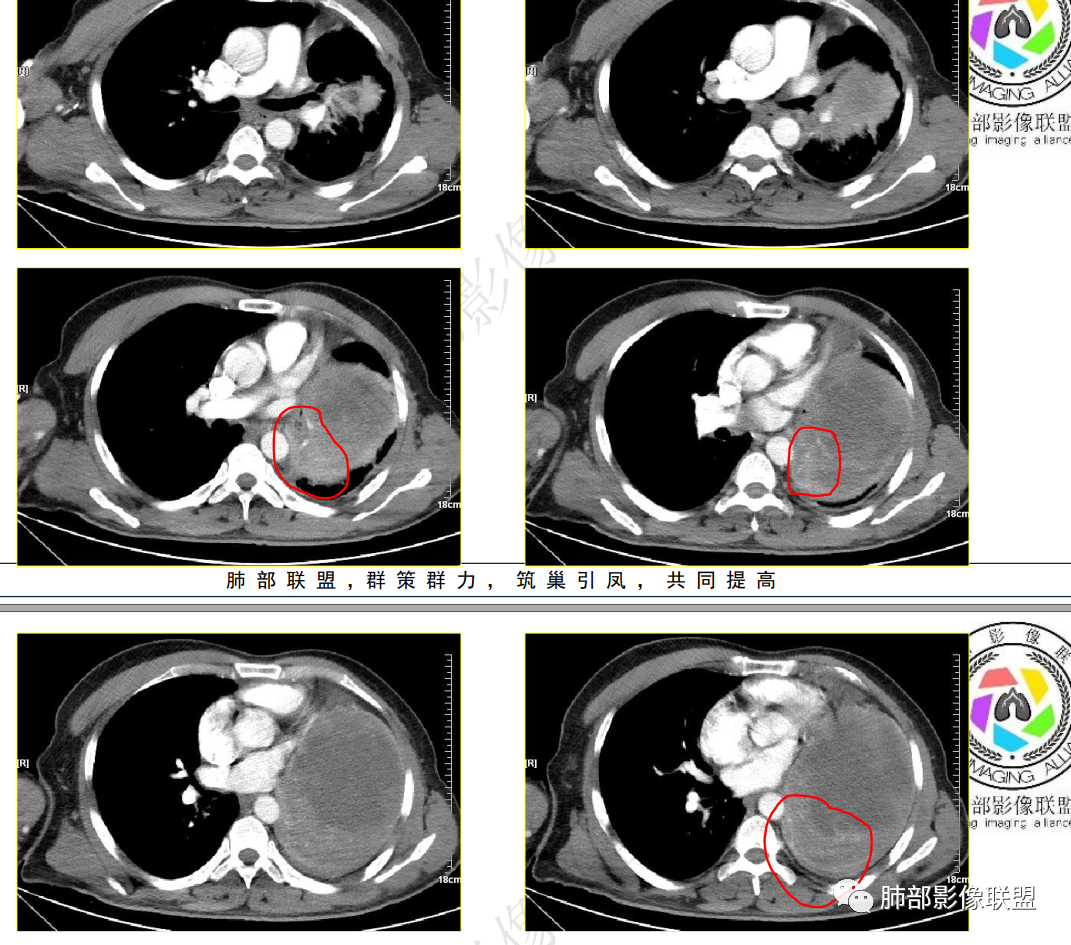

强化方式:多均匀或不均匀明显强化,增强肿瘤内可见迂曲血管影(蛇纹血管等),肿瘤较大可见“地图样”强化。

2.左肺巨大块影,上部边界较清楚,占据胸腔大部,对于左肺,“占据”及“推移”兼而有之,左肺上叶支气管推移狭窄,下叶支气管截断。下肺动脉穿行!

3.病灶密度不均,轻度强化,坏死或液化范围甚大,边界可分辨,部分“壁”可见钙化。

1.无论是肺部还是胸腔“巨大实性密度”块影且边界较清楚者,较少为上皮来源的肺恶性肿瘤,而更符合间叶组织来源的肉瘤。

尤其是病程较长(纵隔移位明显),相对破坏力不强,缺乏远处转移证据的,表明其恶性程度并不那么高。